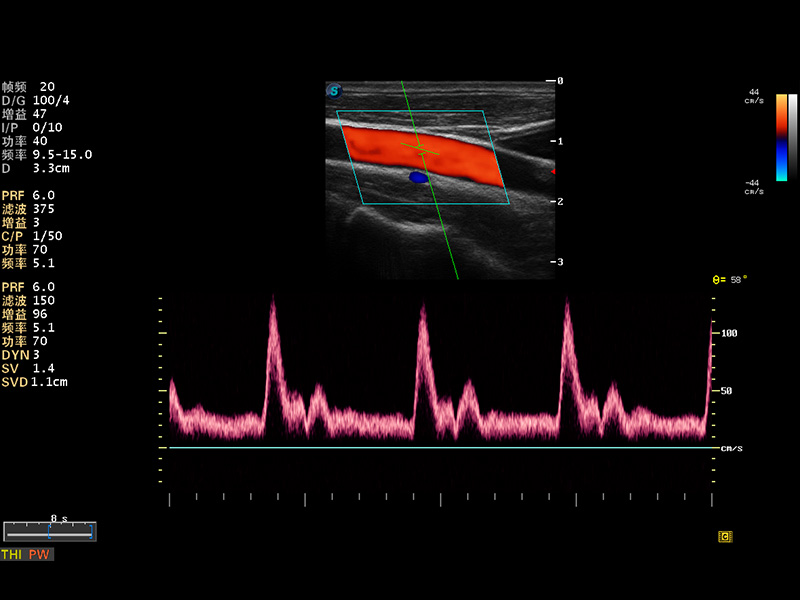

S8 EXP便攜式彩色多普勒超聲診斷儀是開立醫(yī)療研發(fā)的高端全身應(yīng)用型便攜彩超。高通道的VIS平臺(tái)融合可視化(Visual)、智能化(Intelligent)和人性化(Smart)的特點(diǎn),配以開立醫(yī)療自主研發(fā)生產(chǎn)的探頭大家族,使您能夠快速、準(zhǔn)確的獲得病人信息,提高工作效率的同時(shí)減輕疲勞。

成像技術(shù)

多波束形成器